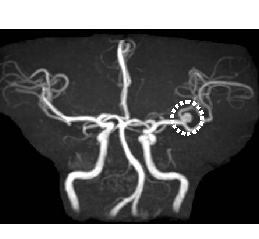

MRA画像

左内頸動脈狭窄

MRA画像

脳動脈瘤